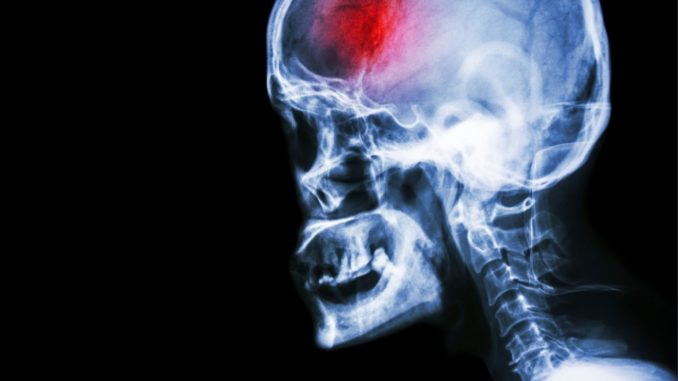

Es sei möglich, dass ihre neue Herzklappe mitverantwortlich für die Schlaganfälle gewesen sei. Sie habe eine etwas raue Oberfläche, an der etwas anhaften könne. Wenn diese Anhaftungen sich lösten, könne es zu plötzlichen Durchblutungsstörungen im Gehirn kommen, sagte Schröder-Köpf der Zeitung.